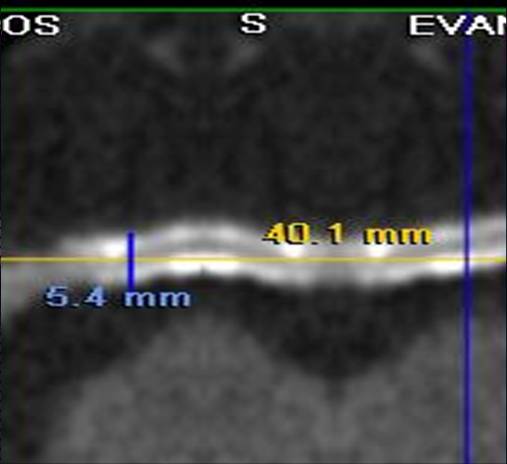

The non-invasive imaging modality of multi-detector computed tomography has dramatically evolved the last ten years and that is due to hardware and software developments. The newer generation of scanners allows increased spatial and temporal resolution that improves the clinical reliability giving further insights into the evaluation of coronary artery disease. Heart morphology imaging followed by studies of myocardial function and assessment of cardiac valves can be performed from the information derived from the data of the coronary artery examination. Also, the venous anatomy of the heart, coronary artery bypass grafts, stents, and cardiac tumors can be imaged and evaluated when necessary. For the beneficial use of this method, entrance criteria for different patient groups need to be set in order to allow improved outcome of multi-detector CT.